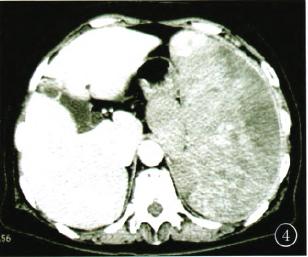

脾-副脾血管肉瘤的ct表现1例

胰腺内副脾的影像学来了